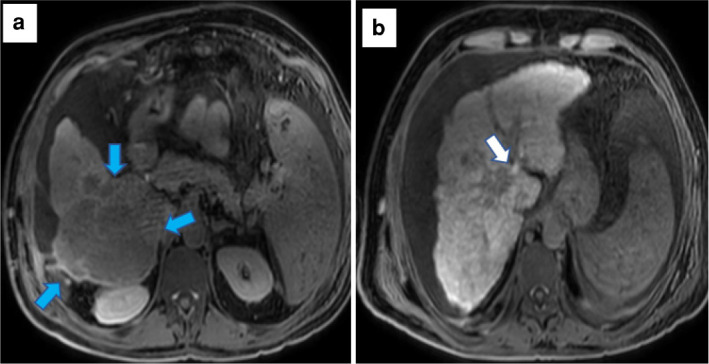

Materials and methods: Between April 2015 and December 2022, the HCC patients who underwent gadoxetic acid-enhanced MRI were analyzed. Three parameters on hepatobiliary phase images were evaluated for FLIS: liver parenchymal enhancement, biliary excretion, and signal intensity of the portal vein. The correlation between Child-Turcotte-Pugh (CTP) classification, the albumin-bilirubin (ALBI) grade, and Fibrosis-4 (F-4) score, and FLIS were analyzed. Receiver operating characteristic curve analysis was performed to demonstrate the cut-off value of FLIS for differentiating between CTP classification and ALBI grade.

Abstract Image